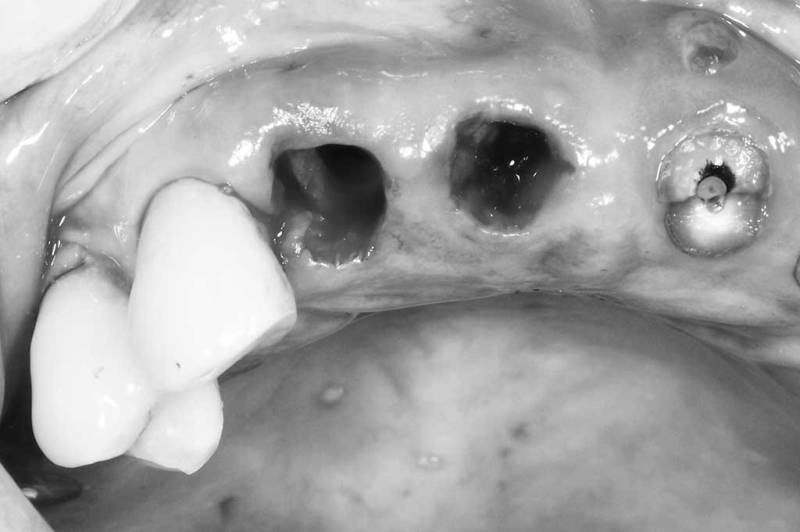

窩洞保存術術中